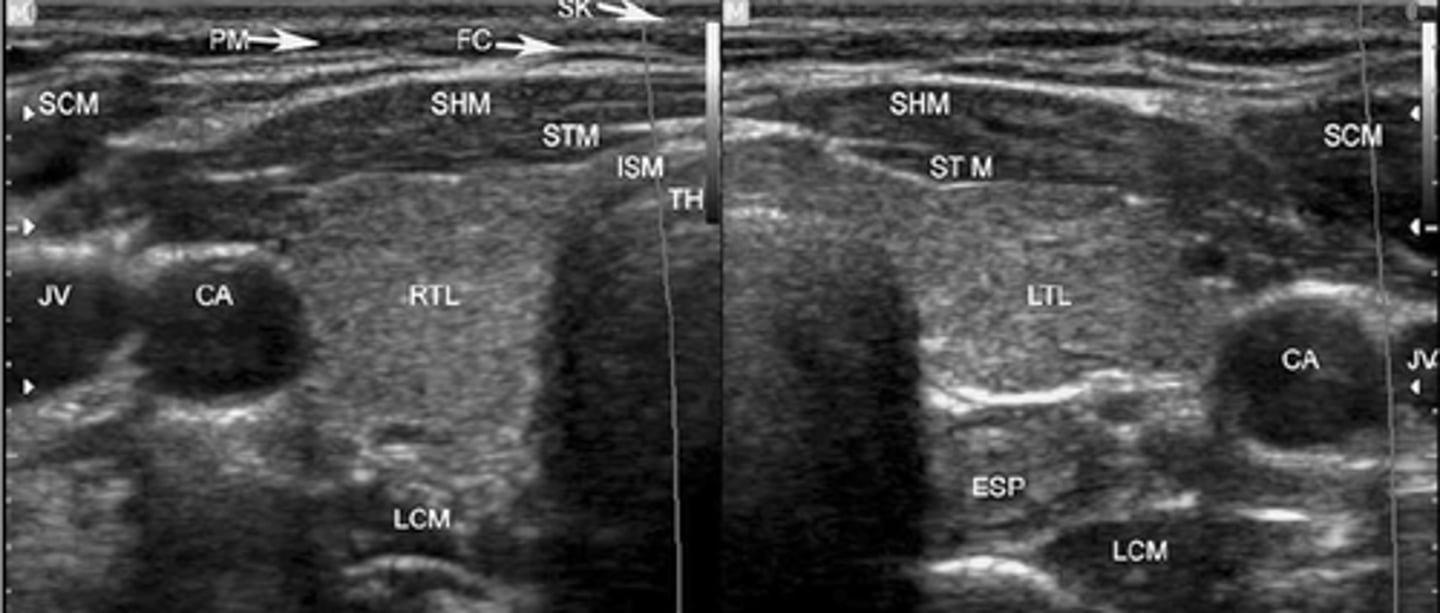

Sonographic Appearance:

-Thyroid lobes and isthmus appear as ____geneous solid structures demonstrating a medium-gray echo pattern with a surrounding thin ____echoic line

-Sternocleidomastoid muscle are _____ and oval in shape appearing ____echoic compared with the normal thyroid gland

-Strap muscles are _____ and ____echoic compared with the normal thyroid gland

-Longus colli muscles appear ____echoic compared with the normal thyroid gland

-Thyroid lobes and isthmus appear as homogeneous solid structures demonstrating a medium-gray echo pattern with a surrounding thin hyperechoic line

-Sternocleidomastoid muscle are large and oval in shape appearing hypoechoic compared with the normal thyroid gland

-Strap muscles are thin and hypoechoic compared with the normal thyroid gland

-Longus colli muscles appear hypoechoic compared with the normal thyroid gland